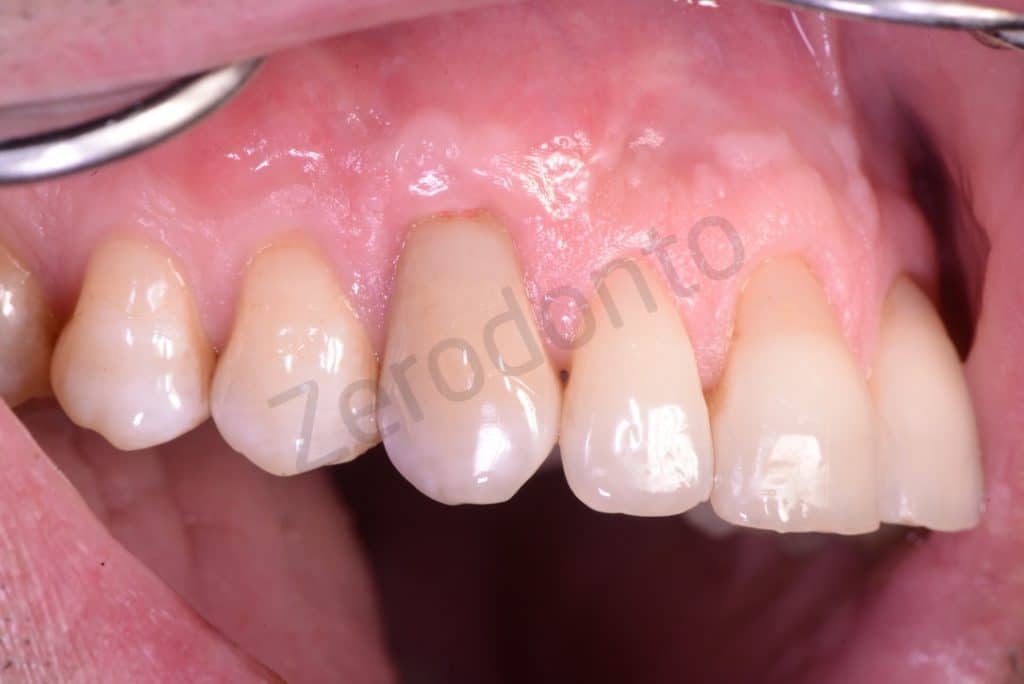

Frontal view

BEFORE AND AFTER BIODENTINE

3 years clinical follow-up